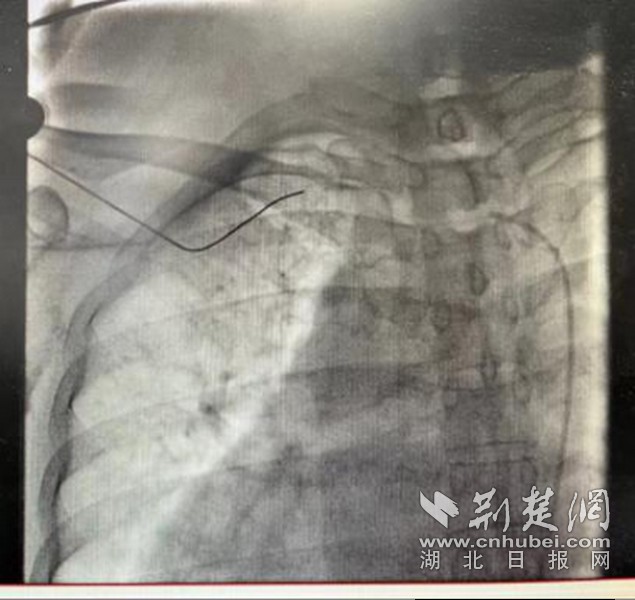

考慮以上種種因素,該院心血管內(nèi)科介入團(tuán)隊(duì)經(jīng)過(guò)認(rèn)真且詳細(xì)的術(shù)前討論,在做好各種預(yù)案,與患者及家屬充分溝通后,決定實(shí)施心臟永久起搏器安置術(shù)。6月19日下午,由醫(yī)院心血管內(nèi)科主任蘭江、副主任辜強(qiáng)、主治醫(yī)師張華、陳文婷、陳明慧等組成的介入團(tuán)隊(duì),為申阿姨實(shí)施了永久起搏器植入術(shù)。手術(shù)歷時(shí)近3小時(shí),蘭江主任團(tuán)隊(duì)克服了患者鎖骨下靜脈變異、需要在造影下重新穿刺等重重難關(guān),最終成功為患者在右側(cè)胸壁植入了永久單腔起搏器,植入后各項(xiàng)參數(shù)良好,術(shù)后患者頭暈癥狀有所改善,無(wú)任何并發(fā)癥,近日已順利康復(fù)出院,患者及家屬對(duì)治療效果非常滿意。

一般而言,普通人的心臟偏左,位于左胸腔,但也有一部分人長(zhǎng)在了右側(cè),其心房、心室和大血管的位置宛如正常心臟的鏡中象,被稱為“右位心”,又稱“鏡面心”,是一種少見(jiàn)的先天性心血管病,在人群中約占1%。而為右位心患者植入永久起搏器,目前國(guó)內(nèi)外僅有個(gè)案報(bào)道。